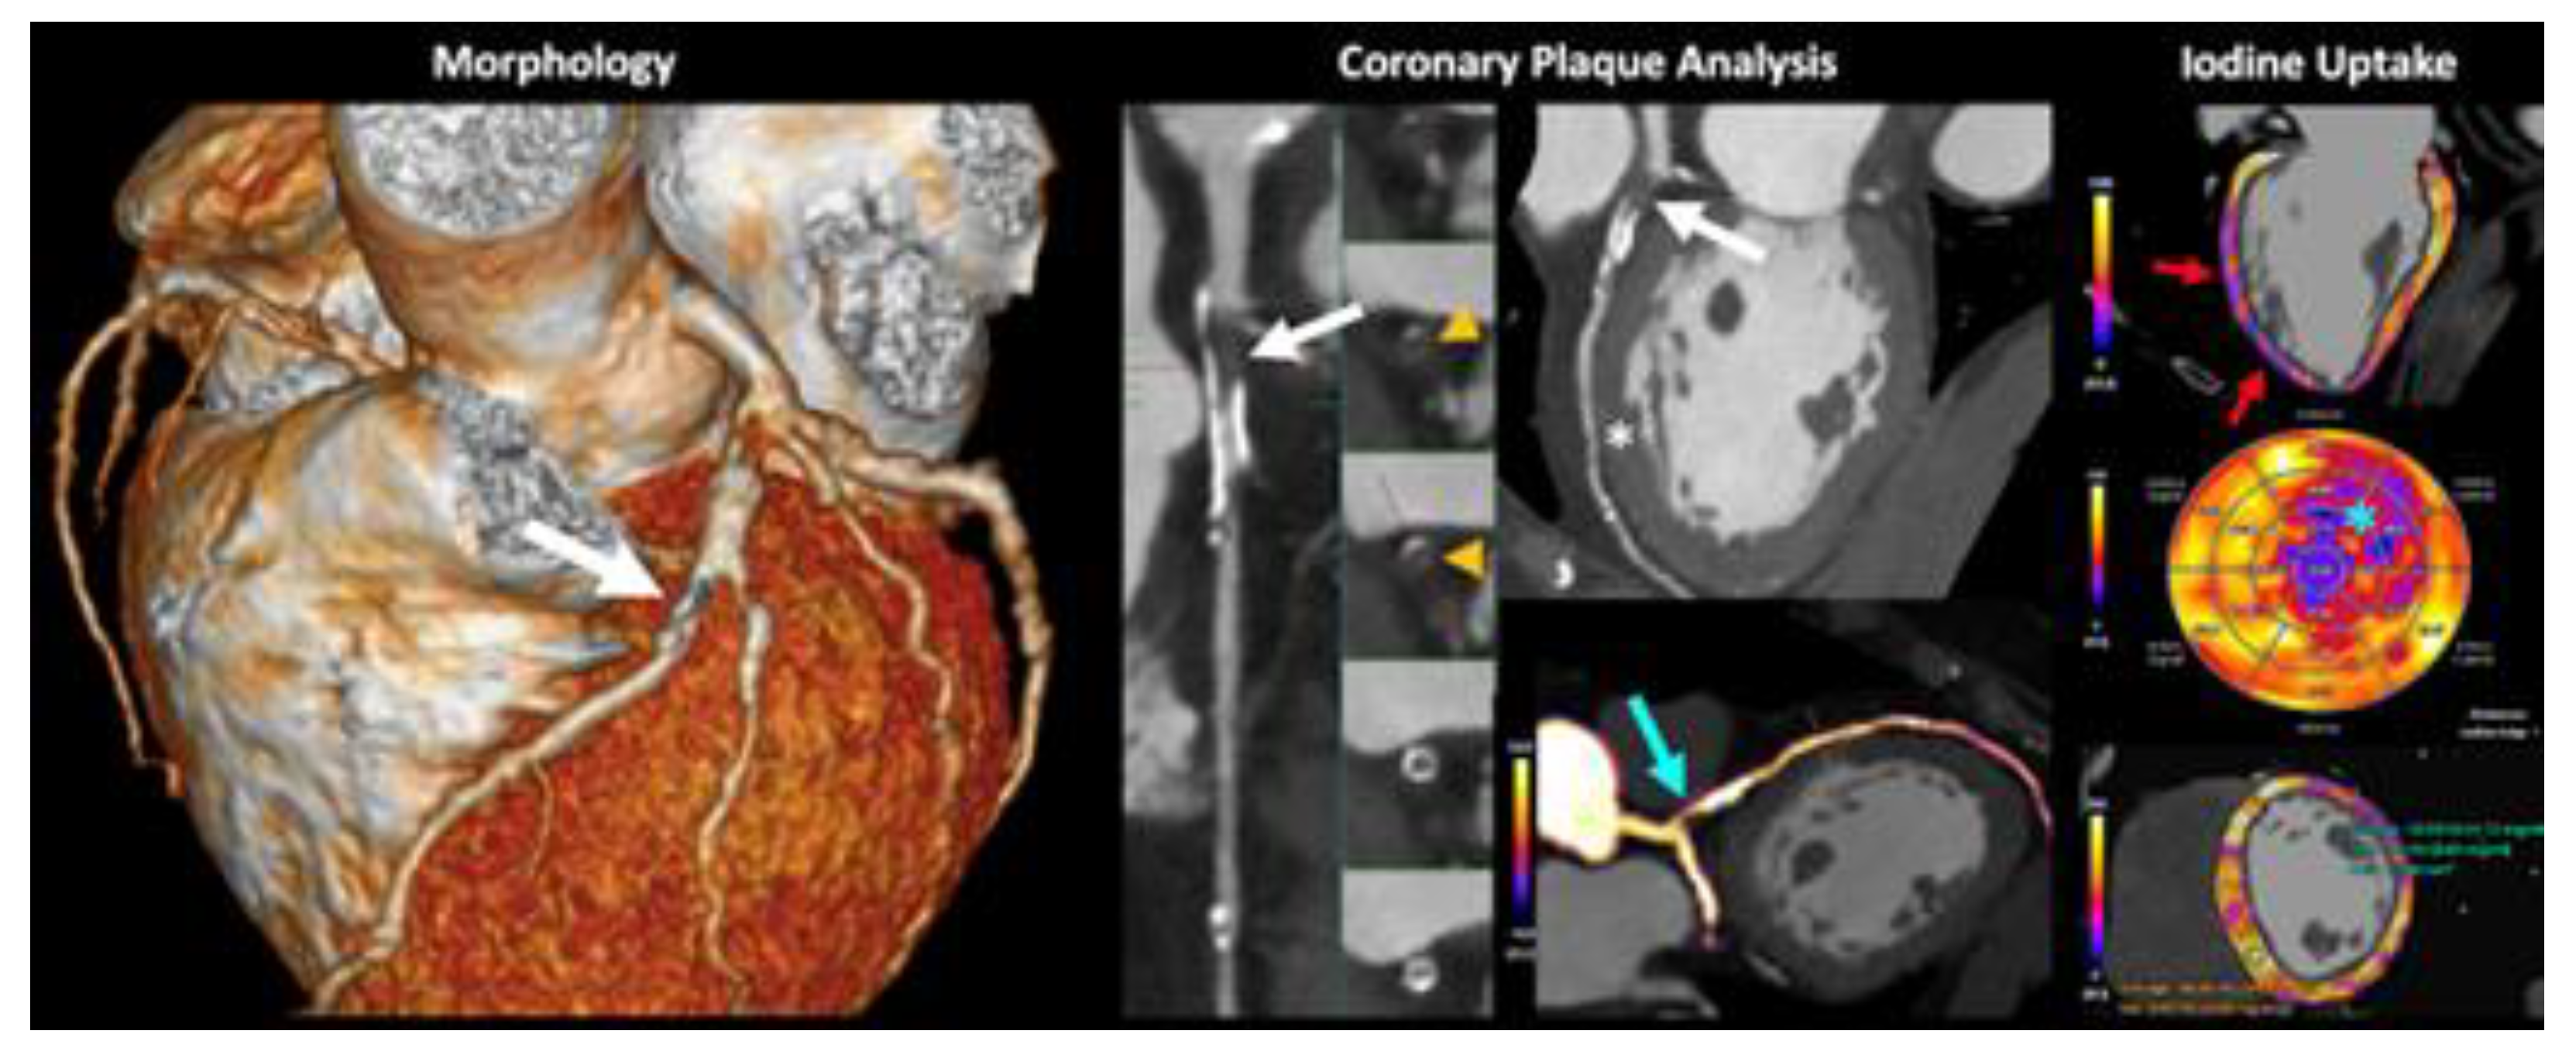

- Danad, I.; Fayad, Z.A.; Willemink, M.J.; Min, J.K. New Applications of Cardiac Computed Tomography: Dual-Energy, Spectral, and Molecular CT Imaging. JACC: Cardiovasc. Imaging 2015, 8, 710–723. [Google Scholar] [CrossRef] [PubMed]

- Dell’aversana, S.; Ascione, R.; De Giorgi, M.; De Lucia, D.R.; Cuocolo, R.; Boccalatte, M.; Sibilio, G.; Napolitano, G.; Muscogiuri, G.; Sironi, S.; et al. Dual-Energy CT of the Heart: A Review. J. Imaging 2022, 8, 236. [Google Scholar] [CrossRef] [PubMed]

- De Santis, D.; Eid, M.; De Cecco, C.N.; Jacobs, B.E.; Albrecht, M.H.; Varga-Szemes, A.; Tesche, C.; Caruso, D.; Laghi, A.; Schoepf, U.J. Dual-Energy Computed Tomography in Cardiothoracic Vascular Imaging. Radiol. Clin. North Am. 2018, 56, 521–534. [Google Scholar] [CrossRef]